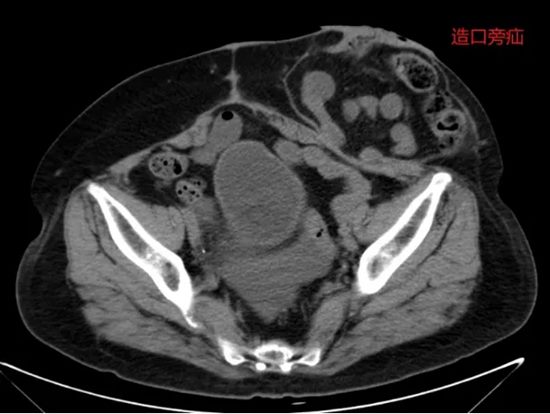

病例四:宫颈癌术后肠瘘+造口旁疝,一次微创手术解决两大难题

640 (3)_副本

病情简述:59岁女性,宫颈癌术后第3天并发乙状结肠瘘。

诊疗破局:团队急诊行腹腔镜手术控制感染并造口。半年后患者要求还纳造口,术前发现合并造口旁疝。经周密规划,在一次腹腔镜手术中同时完成“造口还纳”与“疝修补术”,避免了两次手术创伤。

技术体现:从急诊处理到远期重建,微创外科贯穿始终,体现了系统性治疗的前瞻性。